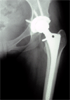

Pre

Op

33 years old female with hip pain due to avascular necrosos hips from chronic steroid ingestion

Xrays